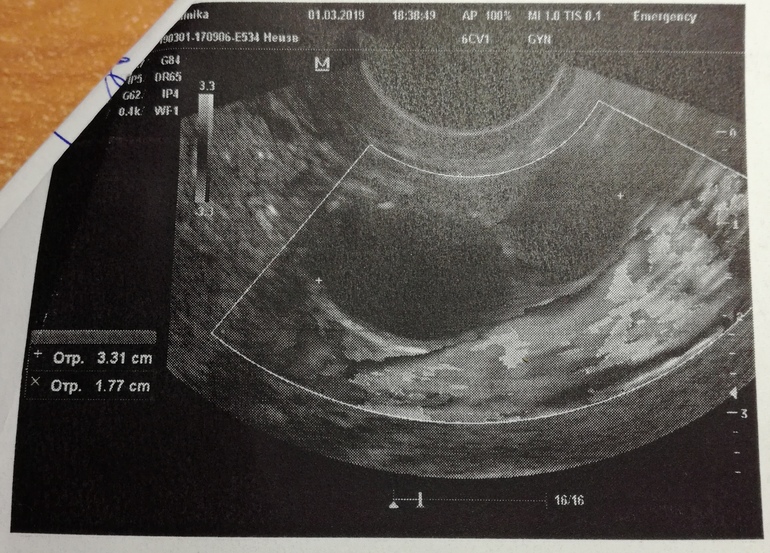

Подскажите можно ли на УЗИ перепутать ДФ и кисту функциональную.

УЗИ на 8дц. Вначале врач УЗист сказала, что два ДФ в ПЯ, 15 и 14 мм, но потом подумав сказала, что все таки это с предыдущего цикла фолликулярные кисты.

В ЛЯ установила ДФ 10мм.